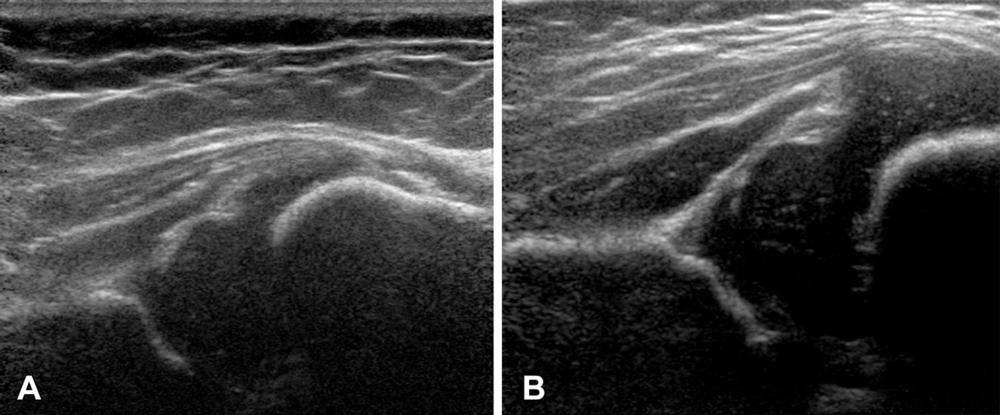

Figure 5. Examples of hip US images acquired with mode 2; no contrast material was used. The presented hips were (A) −1.83 (girl) and (B) +2.12 (girl) standard deviations from the mean shape.

High-res (TIF) version